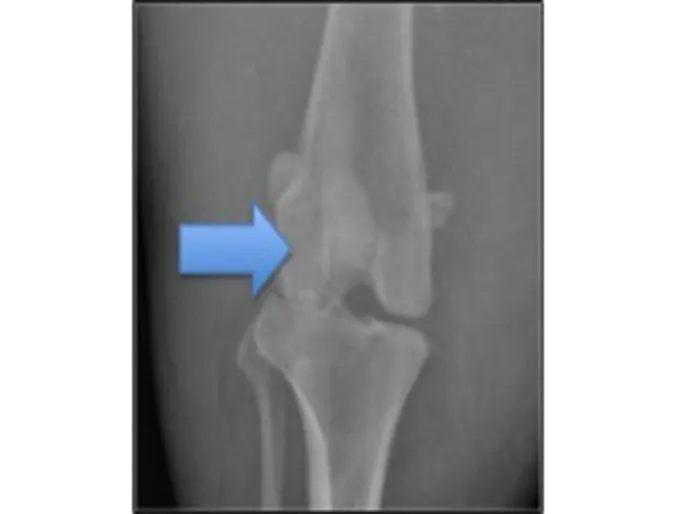

The radiographs above show a normal canine stifle and a stifle with a Grade IV patella luxation. On the normal radiographs the patella, indicated by the blue arrow, is difficult to see as it lies on top of the femur. In the Grade IV MPL the patella, pointed out by the red arrow, is “floating” in space instead of being properly positioned over the femur. In addition, the femur and tibia are abnormally curved. All of this results in hind limb deformity and persistent lameness or an abnormal gait. (Courtesy Dr. Sharon Kerwin of Texas A&M University)